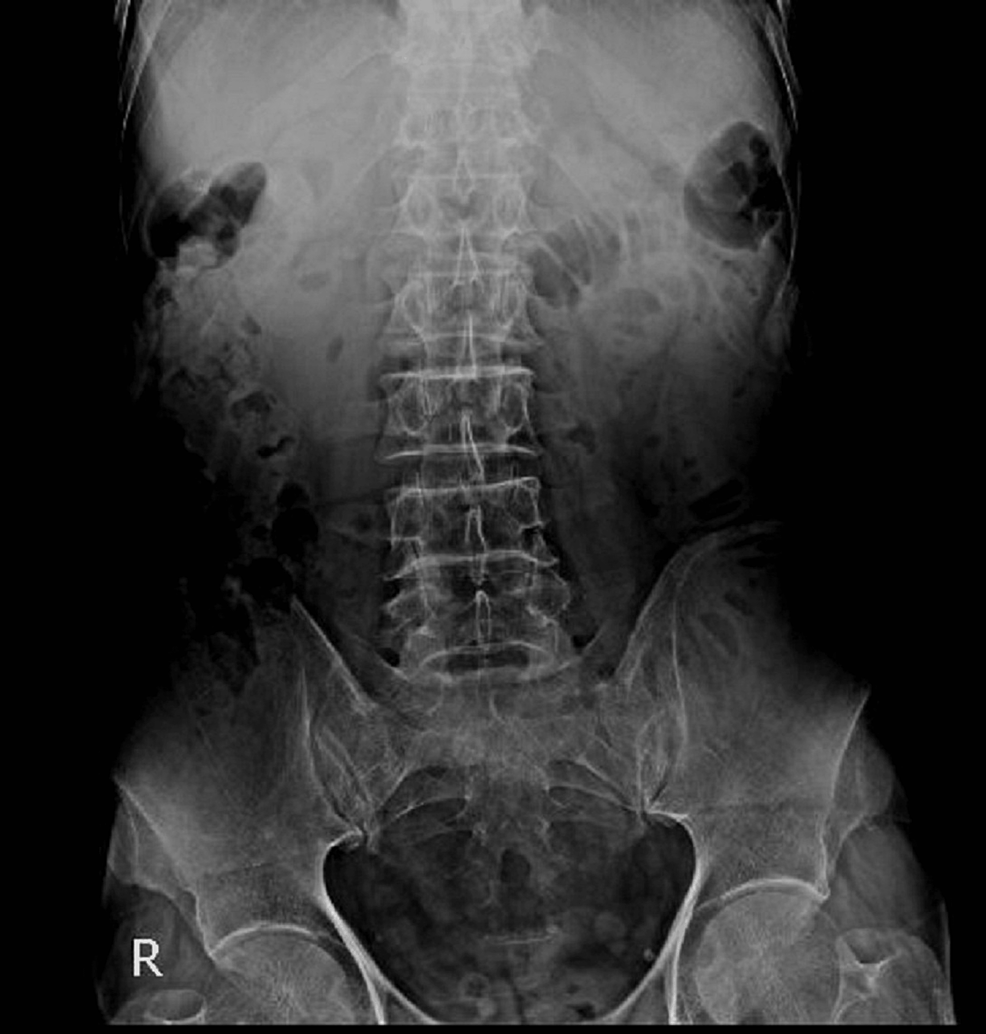

Upright abdominal X-ray showed mildly dilated small bowel loops (Figure 1). An abdominopelvic CT scan with oral contrast was performed. Findings were compatible with gallstone ileus: dilated duodenal and jejunal loops, fistulous tract between gallbladder wall and duodenal bulb, oral contrast leakage to gallbladder lumen, obstructing layering gall bladder stone in the jejunum, and at least two other stones in the gall bladder (Figure 2).

Lassandro et al. found that the Rigler’s triad is observed in 14.8% of cases via plain abdominal radiography, 11.11% of cases on ultrasound examination, and 77.78% on abdominal CT scan [14]. In our patient, the Rigler’s triad was present on the CT scan, but it was not clearly visible on the abdominal X-ray. A correct preoperative diagnosis has been reported only in 50% of cases. Sometimes, gallstone ileus is diagnosed during surgery in patients with an unknown cause of small bowel obstruction [17].